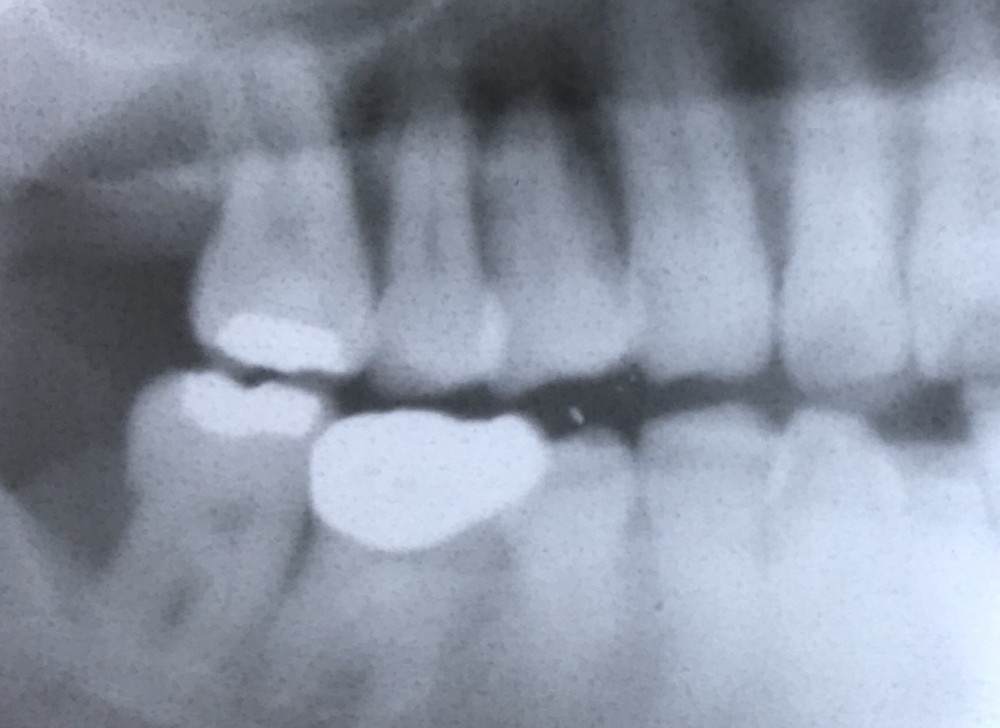

まずは下のレントゲン写真をご覧ください。

この方は、右上の後ろから3番目の歯がかなりグラグラしています。

(画面では左上の後ろから3番目の歯です。レントゲン写真では、鏡とは向きが左右逆になります)

歯根周囲の歯槽骨が吸収したことが原因で、

物を噛み締めることが困難な状態になっています。

あと数ヶ月で自然に抜ける可能性が高いと予想されます。